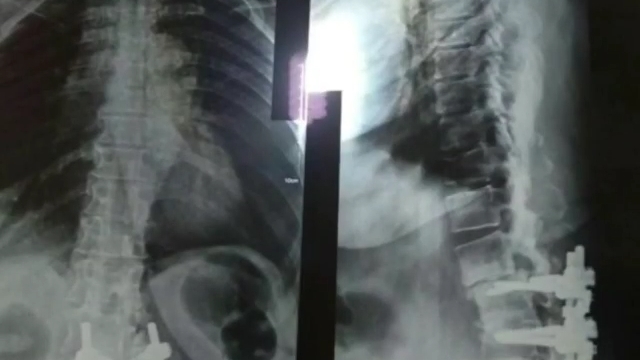

خانم ٦٠ساله ای که چندین سال پیش مورد عمل کمری وسیله گذاری شده بود

و با شکستگی وسیله و اختلال بالانس شدید مراجعه کرده بود

و درد شدید کمری و اندام های تحتانی که توسط دکتر رضا سنجری متخصص جراحی مغز و اعصاب و ستون فقرات بهبود یافت.